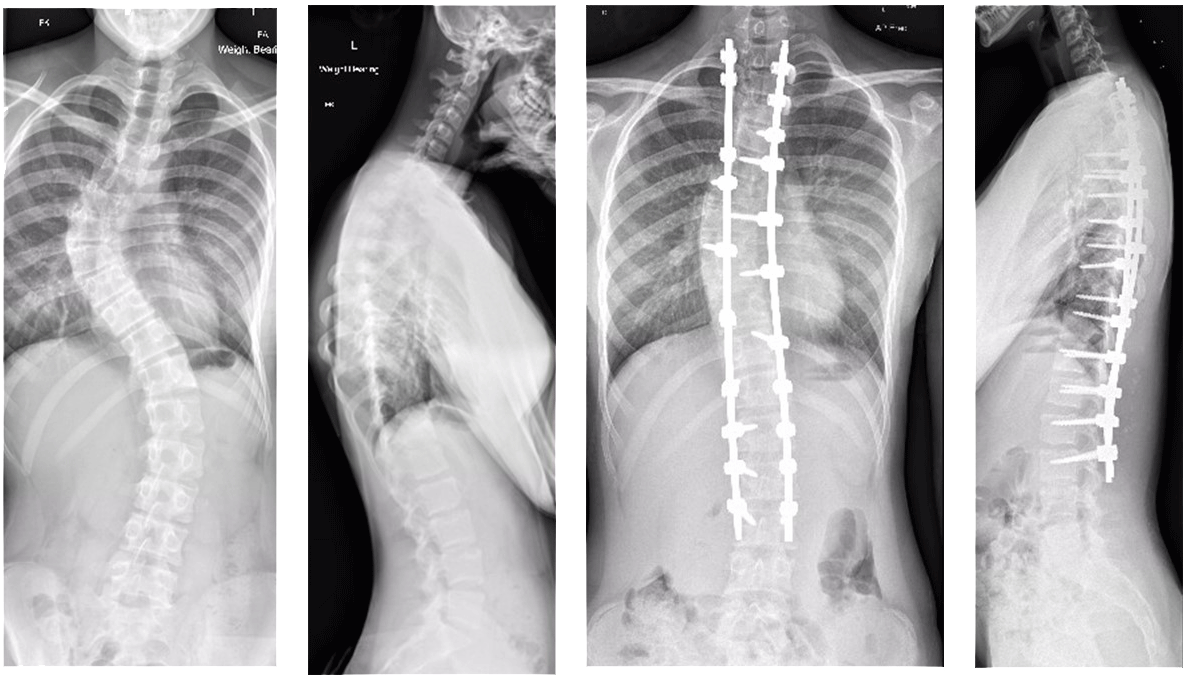

- Chụp X-quang: Hình ảnh X-quang giúp xác định mức độ cong vẹo của cột sống và đo góc lệch.

- Theo dõi định kỳ: Đối với trường hợp cong vẹo cột sống nhẹ, có thể không cần điều trị mà chỉ cần được theo dõi và chụp X-quang định kỳ để kiểm tra xem tình trạng có tiến triển hay không

- Can thiệp phẫu thuật: Bệnh cong vẹo cột sống có thể cần phải can thiệp điều trị phẫu thuật bằng các phương pháp như: phẫu thuật chỉnh hình cột sống, phẫu thuật ghép xương,… trong trường hợp bệnh nặng, không thể điều trị bằng các phương pháp khác